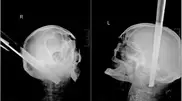

Мужчину с ножкой от табурета в голове спасли в России Мужчину с ножкой от табурета в голове спасли в России Ножка от табурета пробила пациенту полость черепа в затылочной части и прошла на 11 сантиметров вглубь его основания сквозь вещество головного мозга.

21 августа 2013 17:13